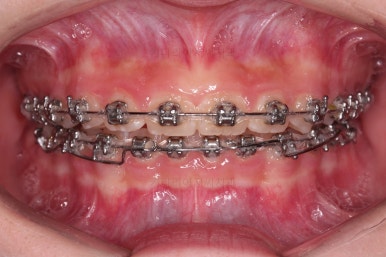

초진 시 입안의 모습입니다.

앞니가 안으로 굽어 들어간 양상인데요. 흔히 "옥니"라고 표현합니다.(뻐드렁니의 반대개념)

전반적으로 치열이 삐뚤삐뚤하고요.

오른쪽 상단 사진을 보시면 어금니의 높이와 앞니의 높이의 차이가 많이 나요.

앞니가 솟구쳐 있는 양상인데요.

그 이유 때문에 어금니로 다물었을 때 위아래 앞니가 많이 겹쳐서 아래 앞니가 아예 보이지 않는 상황이었어요.

이를 "과개교합"이라고 표현합니다.

그리고 전반적으로 아래 치열이 윗니에 비해 뒤로 밀려 있어서, 어금니의 맞물림이 좋지 못하고 듬성듬성해 보이는 상황이었어요.